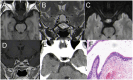

Results: Among the eight cases, the lesions were identified as follows: Solitary fibrous tumor (SFT) in one case, Lymphocytic hypophysitis (LYH) in one case, Cavernous sinus hemangiomas (CSH) in one case, Ossifying fibroma (OF) in two cases; Sphenoid sinus mucocele (SSM) in one case, Pituitary abscess (PA) in two cases. All patients underwent successful EETS, and their diagnoses were confirmed through pathological examination. Postoperatively, all patients had uneventful recoveries without occurrences of diabetes insipidus or visual impairment.